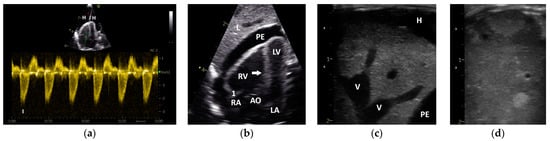

Figure 4.

PW Doppler sonographic blood flow profiles of the aorta (a) and pulmonary arteries (b–d) of Congo grey parrots without sonographic evidence of heart disease (GPs from group 1). The acceleration phase of the blood flow is visible in red and the deceleration phase in blue in (a,b). A sample gate is placed in the area of the aortic (a) or pulmonary valve (b–d); AC: angle correction. The colour scale on the right side of the images is calibrated in m s−1.

However, in GPs with left heart (group 2) and/or right heart failure (group 3), we found a shortening of the AP of their PAFP (Table 5, Table 6 and Table 7). The PAFP showed a short AP and thus the PAFP looks similar to that of the aorta, especially in advanced cases (Figure 5).

Figure 5.

PW Doppler sonographic blood flow profiles of the pulmonary artery of Congo grey parrots with left and right heart failure ((a–f); GPs from group 3). In all presented cases, the abnormally short acceleration phase (AP) of the pulmonary blood flow profile (PAFP) is visible; RV: right ventricle; LV: left ventricle; PA: pulmonary artery; H: hepatoperitoneal cavity effusion; 1: Doppler signal of the pulmonary valve, with a sample gate placed in the area of the pulmonary valve; AC: angle correction. The colour scale on the right side of the images is calibrated in m s−1.

In one case from the group of GPs without sonographic evidence of heart disease (group 1), a PAFP with a very short AP, causing it to look similar to the AOFP, which was associated with a nodular liver disease (Figure 3), was found. In some GPs, a change in the shape of the PAFP was recognizable and connected to a worsening of the apparent disease, which led to a new grouping. For example, a clear change in the shape of the PAFP in connection with the development of a pulmonary insufficiency (Figure 2) and right heart dilatation (right heart failure) over one year is presented in Figure 6.

Figure 6.

PW Doppler sonographic blood flow profiles of the pulmonary artery of a Congo grey parrot that developed right heart failure over the course of one year: (a) a symmetric blood flow profile of the pulmonary artery (PAFP), without signs of heart failure, and (b) the shape of the PAFP a year later, with a short acceleration phase seen in conjunction with the development of right heart failure displayed as right ventricular dilatation and an insufficiency of the pulmonary valve. I: insufficiency jet; 1: Doppler signal of the pulmonary valve, with a sample gate placed in the area of the pulmonary valve; AC: angle correction.